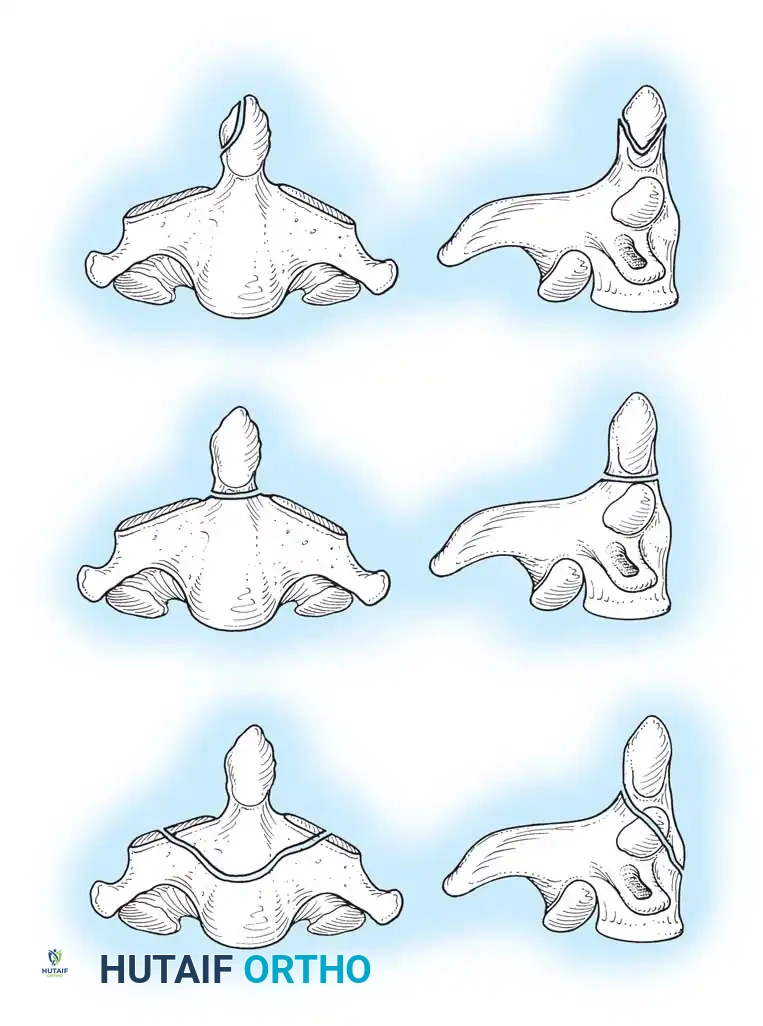

Compressive Extension (Five Stages)

Resulting from a posterior-to-anterior force vector with the neck extended.

* Stage 1: Unilateral vertebral arch fracture with or without anterior rotatory displacement. May present as a "transverse facet" on AP radiographs.

* Stage 2: Bilaminar fractures without other tissue failure, typically occurring at multiple contiguous levels.

* Stage 3: Bilateral vertebral arch fractures (articular processes, pedicles, or lamina) without vertebral body displacement.

* Stage 4: Bilateral vertebral arch fractures with partial anterior displacement of the vertebral body.

* Stage 5: Bilateral vertebral arch fracture with full vertebral body width displacement anteriorly. The posterior arch remains behind, while the centrum shears off the anterosuperior portion of the vertebra below.